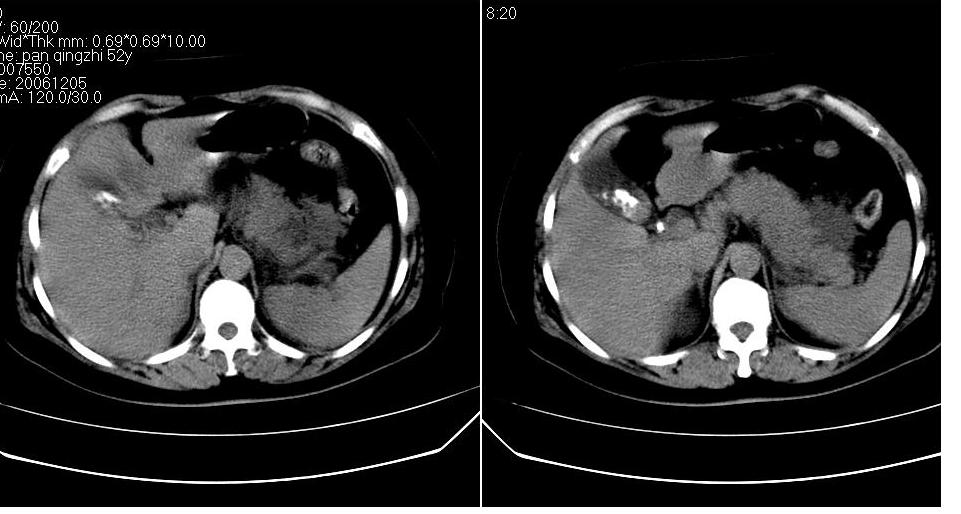

女 52岁,腹痛两天,无其它不适。

胆囊结石 胰腺炎伴胰尾假性囊肿形成.

支持除胰腺假性囊肿外的一切诊断,胰腺低密度应该是坏死。

胆囊结石,胆总管结石.胰腺炎,胰尾假囊肿形成.

胰头部囊状影是十二指肠。左侧肾前筋膜增厚、少量积液,胰腺增大,边缘模糊,支持胰腺炎。

1、慢性胆囊炎,胆囊结石、胆总管结石。诊断依据:胆囊内、胆总管内见高密度影,胆囊已有萎缩,说明时间已较长,胆囊壁有增厚。

2、胆源性胰腺炎,诊断依据:同1外+左肾周筋膜增厚,肾前间隙积液,胰腺肿大。